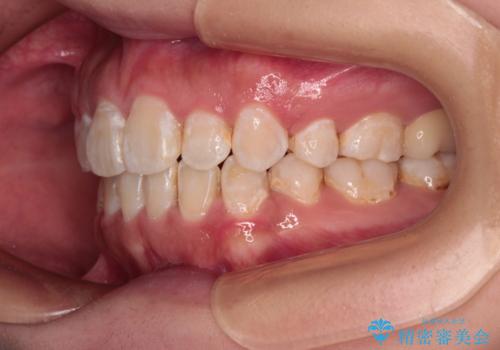

- 前歯のクロスバイトと、口元が閉じにくいとのことで来院された患者様です。

口元の突出感を改善する必要があるため、上下左右の第1小臼歯4本を抜歯し、ワイヤー装置にて矯正治療を行うこととしました。

むし歯のリスクが高かったため、治療が長期化しないように心がけました。

当初の予定通り、2年強で無事に治療を終えることができました。